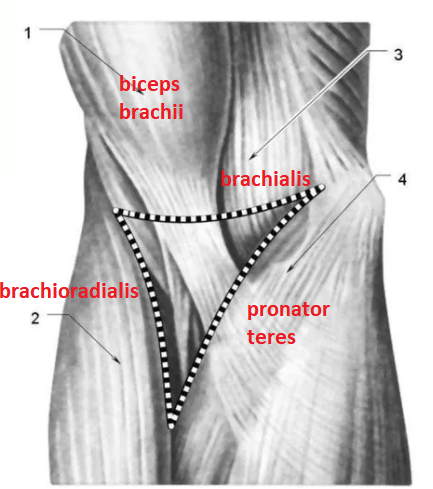

Анатомия и функции мышцы brachioradialis